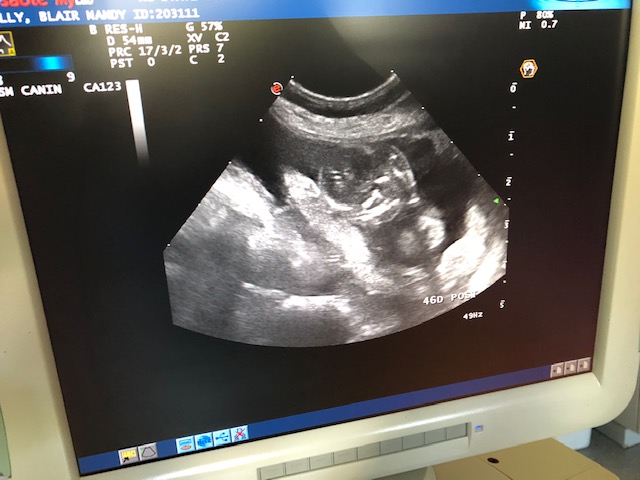

16 Oct 2018

Ultrasound today showed that Mandy is pregnant. Two healthy puppies were seen and one reabsorption site. (Instead of miscarriages, dogs reabsorbs fetuses.) Because of the reabsorption, we pulled some blood from Mandy to check her progesterone level. For breeding, you want to see the progesterone level rise. But for pregnancy you want to see the progesterone level slowly fall. But too fast a fall is bad.

Estimated due date is around 18 November.